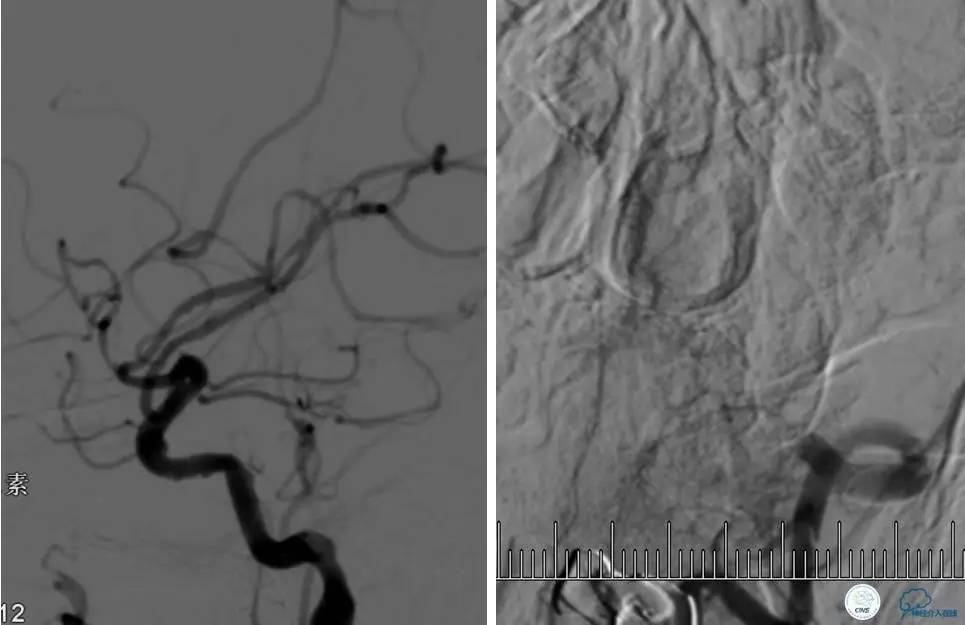

造影评价血管、判断闭塞段,微导丝小心穿过闭塞段,微导管造影,交换技术,球囊扩张,Enterprise支架。在后扩张时导丝刺破M3段血管,蛛网膜下腔出血(SAH)。

微导管进入破裂血管,栓塞弹簧圈1枚,出血停止,结束手术。继续双抗,术后2天肌力2级,神经功能恢复明显加快。

术后即刻和6天后CT,患者无明显临床症状。

半年后复查造影,无支架内再狭窄,可见弹簧圈,患者恢复至自己柱杖行走。